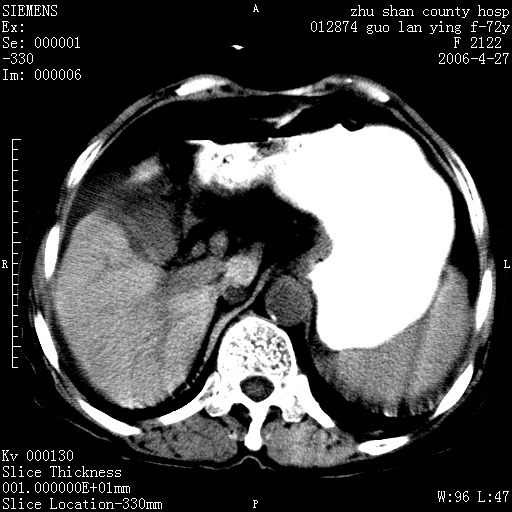

平扫所见:胆囊区两点壮高密度影,灶周有伪影{请问楼主患者有手术病史?}。肝实质内未见明显异常{建议强化或mri}.腹腔有少量积液,脾明显增大.右肾形态似不规则?

腹腔内示积液征,脾脏略增大,肝脏由于运动伪影较多,影响观察,内未见明显高密度区,胆囊内示两处高密度结石。胃窦部壁轻度增厚。另外,肝脏的前缘似有游历气体。不知病人的临床如何?有必要做胃的检查,还有,看看骨窗是否有腹腔游离气体还是肠管影响的。

肝脏缩小,脾脏增大,肝脾外缘及胆囊窝液性密度影,肝脾ct值正常,胆囊区见两个类圆形高密度影,下腔静脉前方类圆形软组织密度影为肝脏岛叶,胃幽门区见软组织密度影,十二指肠钡剂充盈不好.

1:腹水2:胆囊结石3肝硬化?(不确定,请结合临床)4幽门区占位?(建议胃肠透视)

肝硬化,脾大,少量腹水

肝硬化、腹水、脾大,胆囊结石可以肯定。只是肝右叶两个低密度有必要增强确定一下;排除小肝癌。